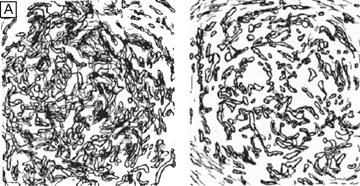

The corneal stroma is maintained by a closed, highly-organized syncytium of keratocytes communicating with each other through gap junctions present on their long dendritic processes.68 Keratocytes occupy 10% to 40% of the stromal volume (decreases from 40% in infancy to 10% in adulthood) that on two-dimensional, cross-sectional views appear as flattened (cell body = 20 μm in length × 1 μm in height), quiescent (i.e., scant intracytoplasmic organelles) cells lying between corneal lamella (Fig. 16A, B). In actuality, keratocytes are three-dimensional, stellate-shaped cells composed of a cell body (≅1 × 15 × 20 μm) with numerous dendritic-processes that extend up to 50 μm in length from the cell body. Two-dimensional tangential sections of the normal cornea suggest that these cells are more highly metabolically active in the resting state than initially presumed; in tangential sections (cell body view = 15 μm width × 20 μm), an abundance of cytoplasmic organelles is commonly seen (Fig. 16C, D).69

Fig. 16. Light and TEM micrographs shown in cross and frontal-sectional views of the cellular corneal stroma demonstrating differences in the appearance of keratocytes depending on the cut, or perspective, of the section. (A) Cross-sectional light microscopy shows that keratocytes are primarily obliquely aligned to corneal surface in the anterior one-third of cellular corneal stroma and are aligned parallel to the corneal surface in the posterior two-thirds. (B) Cross-sectional TEM additionally shows that keratocyte nuclei occupy most of the area of the keratocyte seen in this perspective with only a thin rim of surrounding cytoplasm that contains only small numbers of cytoplasmic organelles. (C) From a tangential perspective, frontal-section light microscopy shows that keratocytes are arranged in a circular fashion. (D) Frontal-section TEM additionally shows that supposedly quiescent keratacytes may be more active in the baseline state than initially thought as an extensive amount of cytoplasmic organelles can be seen in this view. M, mitochondria; RER, rough endoplasmic reticulum; V, vacuoles. *Main portion of nucleus that contains nucleolus. (Modified from Muller LJ, et al. Novel aspects of the ultrastructural organization of human corneal keratocytes. Invest Ophthalmol Vis Sci 36:2557, 1995.)

Tangential sections also have shown more clearly that the anterior stromal keratocytes contain twice the number of mitochondria than the posterior two-thirds of the stroma, which correlates with the oxygen tension levels in the cornea. It also has demonstrated that a higher density or volume of cells reside in the anterior stroma than in the mid or posterior stroma (Fig. 17). Moreover, these views make it easy to appreciate that, in all levels, the keratocytes are highly spatially-ordered as they turn in a clockwise direction like a corkscrew.

Fig. 17. (A) Reconstruction of keratocyte outlines seen in frontal-section in the anterior and posterior thirds of the cellular corneal stroma. (Modified from Muller LJ, et al. Novel aspects of the ultrastructural organization of human corneal keratocytes. Invest Ophthalmol Vis Sci 36:2557, 1995.) (B) Fluorescent-dye spreading between many adjacent keratocytes in rabbit (center left) and human corneas (center right), which demonstrates the intimate importance of gap junctions in how keratocytes communicate with one another. (From Watsky MA. Keratocyte gap junctional dye spread in normal and wounded rabbit corneas and human corneas. Invest Ophthalmol Vis Sci 36:S22, 1995.) (C) Mean keratocyte density along the depth of central cellular corneal stroma. Notice the zone of increased density the closer one gets to the epithelial-stromal junction. Perhaps this is due to baseline, normal epithelial-stromal interactions. (From Patel SV, et al. Normal human keratocyte density and corneal thickness measurement by using confocal microscopy in vivo. Invest Ophthalmol Vis Sci 42:333, 2001.)